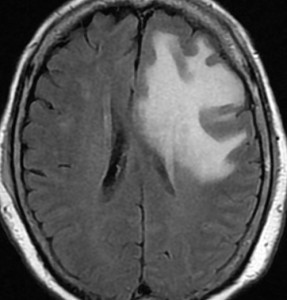

典型的な転移性脳腫瘍(単発)のMRI

腺癌の左前頭葉転移です。左のガドリニウム造影剤を使った画像では腫瘍が白く写っています。腫瘍の内部が一部壊死しているので黒っぽく見えます。右はフレア画像です。腫瘍の周囲の脳が腫れて脳浮腫(白く滲むようなところ)を生じています。

開頭手術で摘出した半年後の画像です。腫瘍は再発していなくて,脳の腫れも引いています。転移が発見された時には,見当識障害などの左前頭葉症状が強かったし,摘出がとても簡単な場所だったので手術しました。線状皮膚切開・小開頭ですから1時間くらいの簡単な手術です。でも,26mmくらいでしたから,定位放射線治療も可能なものでした。この患者さんは幸いなことに半年で再発していませんが,開頭手術による摘出だけだと同じ場所からまた再発することもあり,それから放射線治療を加えなくてはならないこともあります。個々の判断は難しいのですが,基本的には開頭手術より定位放射線治療のほうがいいと考えて下さい。